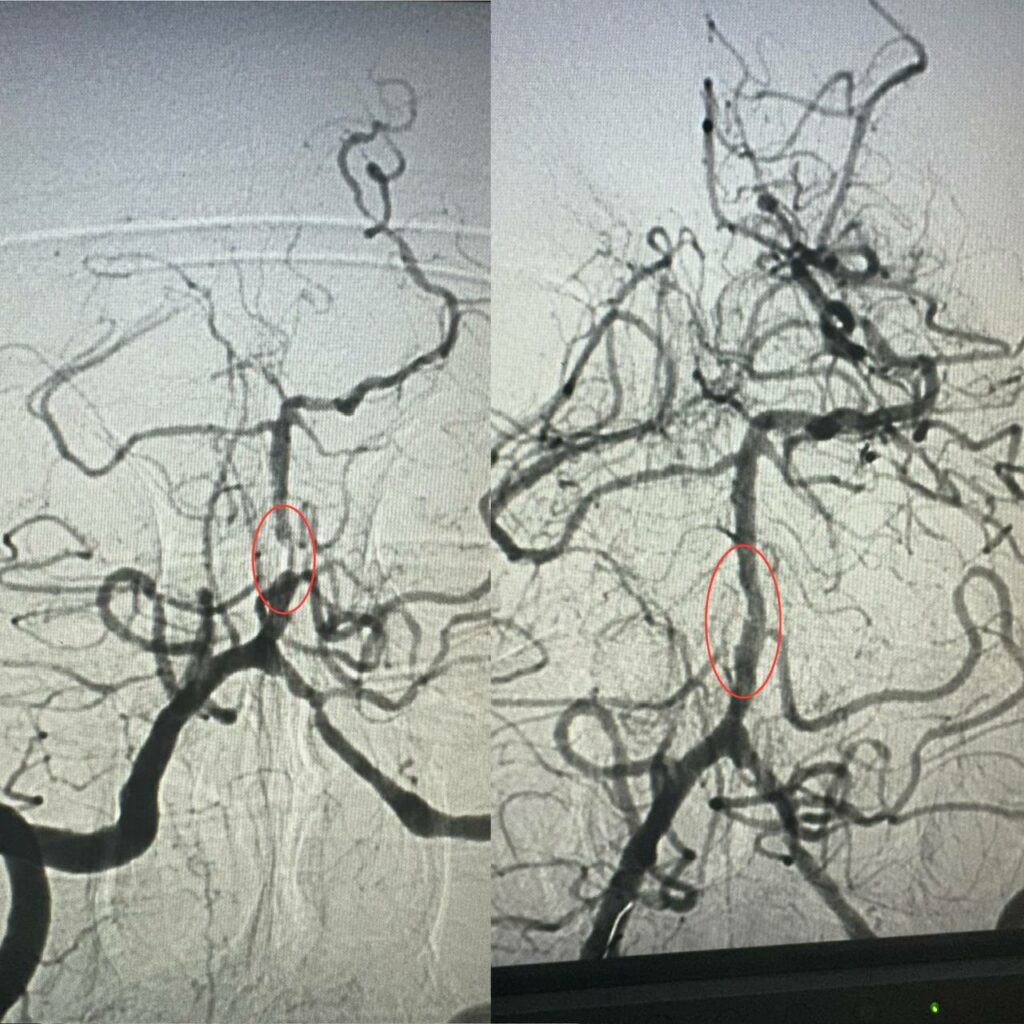

Як розповів завідувач рентгенендоваскулярним блоком лікарні Олександр Скрипка, це був один з найскладніших випадків – ураження стовбурової частини мозку. Базилярна артерія була майже повністю закрита атеросклеротичною бляшкою. Такі інсульти належать до найбільш небезпечних.

Фахівці прийняли рішення провести ангіопластику артерії. Десята лікарня має досвід такої методики лікування в кардіології при атеросклерозі коронарних судин, але застосування її для мозкових судин – це іноваційна технологія для України.